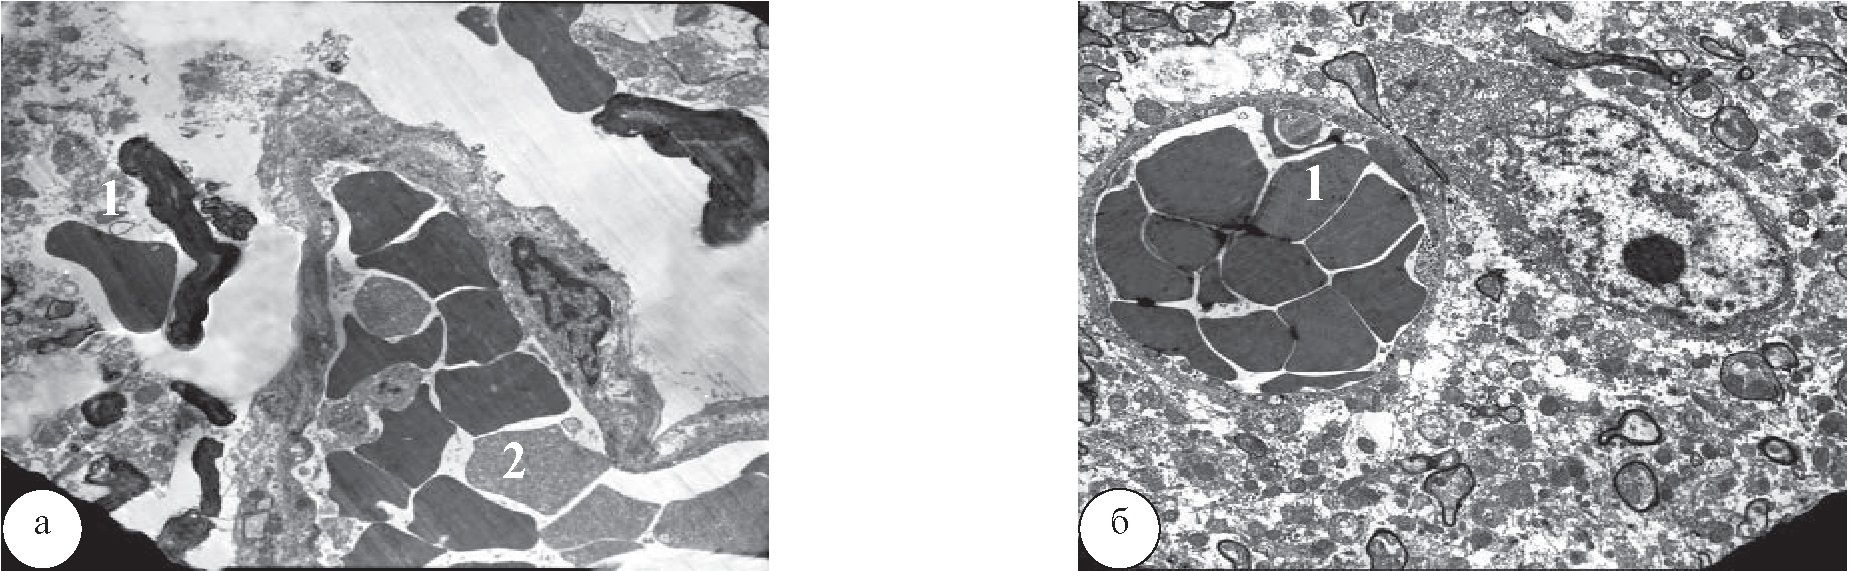

В МВ проводящих путей СМ после ЭН у крыс КГ были обнаружены признаки миелинопатии в виде расслоения слипшихся ламелл миелина и их фрагментации. ОЦ были как сохранными, так и дистрофически измененными по темному типу. В МВ вблизи сосудов также были выявлены признаки миелинопатии, а в БМВ обнаруживалась умеренная либо выраженная аксонопатия по светлому типу (рис. 7а).

Через 1 месяц лечения крыс после ЭН в МВ часто не было признаков миелинопатии и аксонопатии, а их ОЦ были заполнены нейрофибриллами и митохондриями с типичной структурой. В МВ рядом с пролиферирующими ОДЦ ОЦ имели обычную плотность, но их миелиновые оболочки были тоньше и плотнее. В некоторых МВ миелиновые ламеллы были разволокнены, а перехваты Ранвье изменены. В ряде МВ и БМВ наблюдалась аксонопатия по светлому типу; иногда встречались МВ с признаками ремиелинизации за счет внутреннего мезаксона (рис. 7б).

Рис. 7. Миелиновые волокна проводящих путей СМ крыс в области поясничного утолщения после ЭН: а – МВ крысы КГ. Визуализируются аксонопатия в виде просветления ОЦ и миелинопатия в виде слипания ламелл миелина, ув. ×4000; б – МВ крысы после лечения с умеренно измененными ОЦ и ремиелинизацией (1), ув. ×16000

Через 1 месяц после ЭН у крыс КГ в ткани СМ изредка находились свободные эритроциты, что является признаком локальных нарушений гематоэнцефалического барьера. В просвете капилляров эритроциты часто располагались в виде монетных столбиков (капилляростаз) (рис. 8а). В сосудах СМ у крыс после ЭН с последующим лечением с помощью ТКМС, как и без лечения, отмечался капилляростаз, но свободных эритроцитов в нейропиле не было (рис. 8б).

Рис. 8. Капилляры поясничного утолщения спинного мозга крыс после ЭН: а – крыса КГ после ЭН. Видны свободные эритроциты в нейропиле (1) и капилляростаз (2), ув. ×3150; б – крыса после ЭН с последующим лечением с помощью ТКМС. Наблюдается капилляростаз (1), ув. ×3150